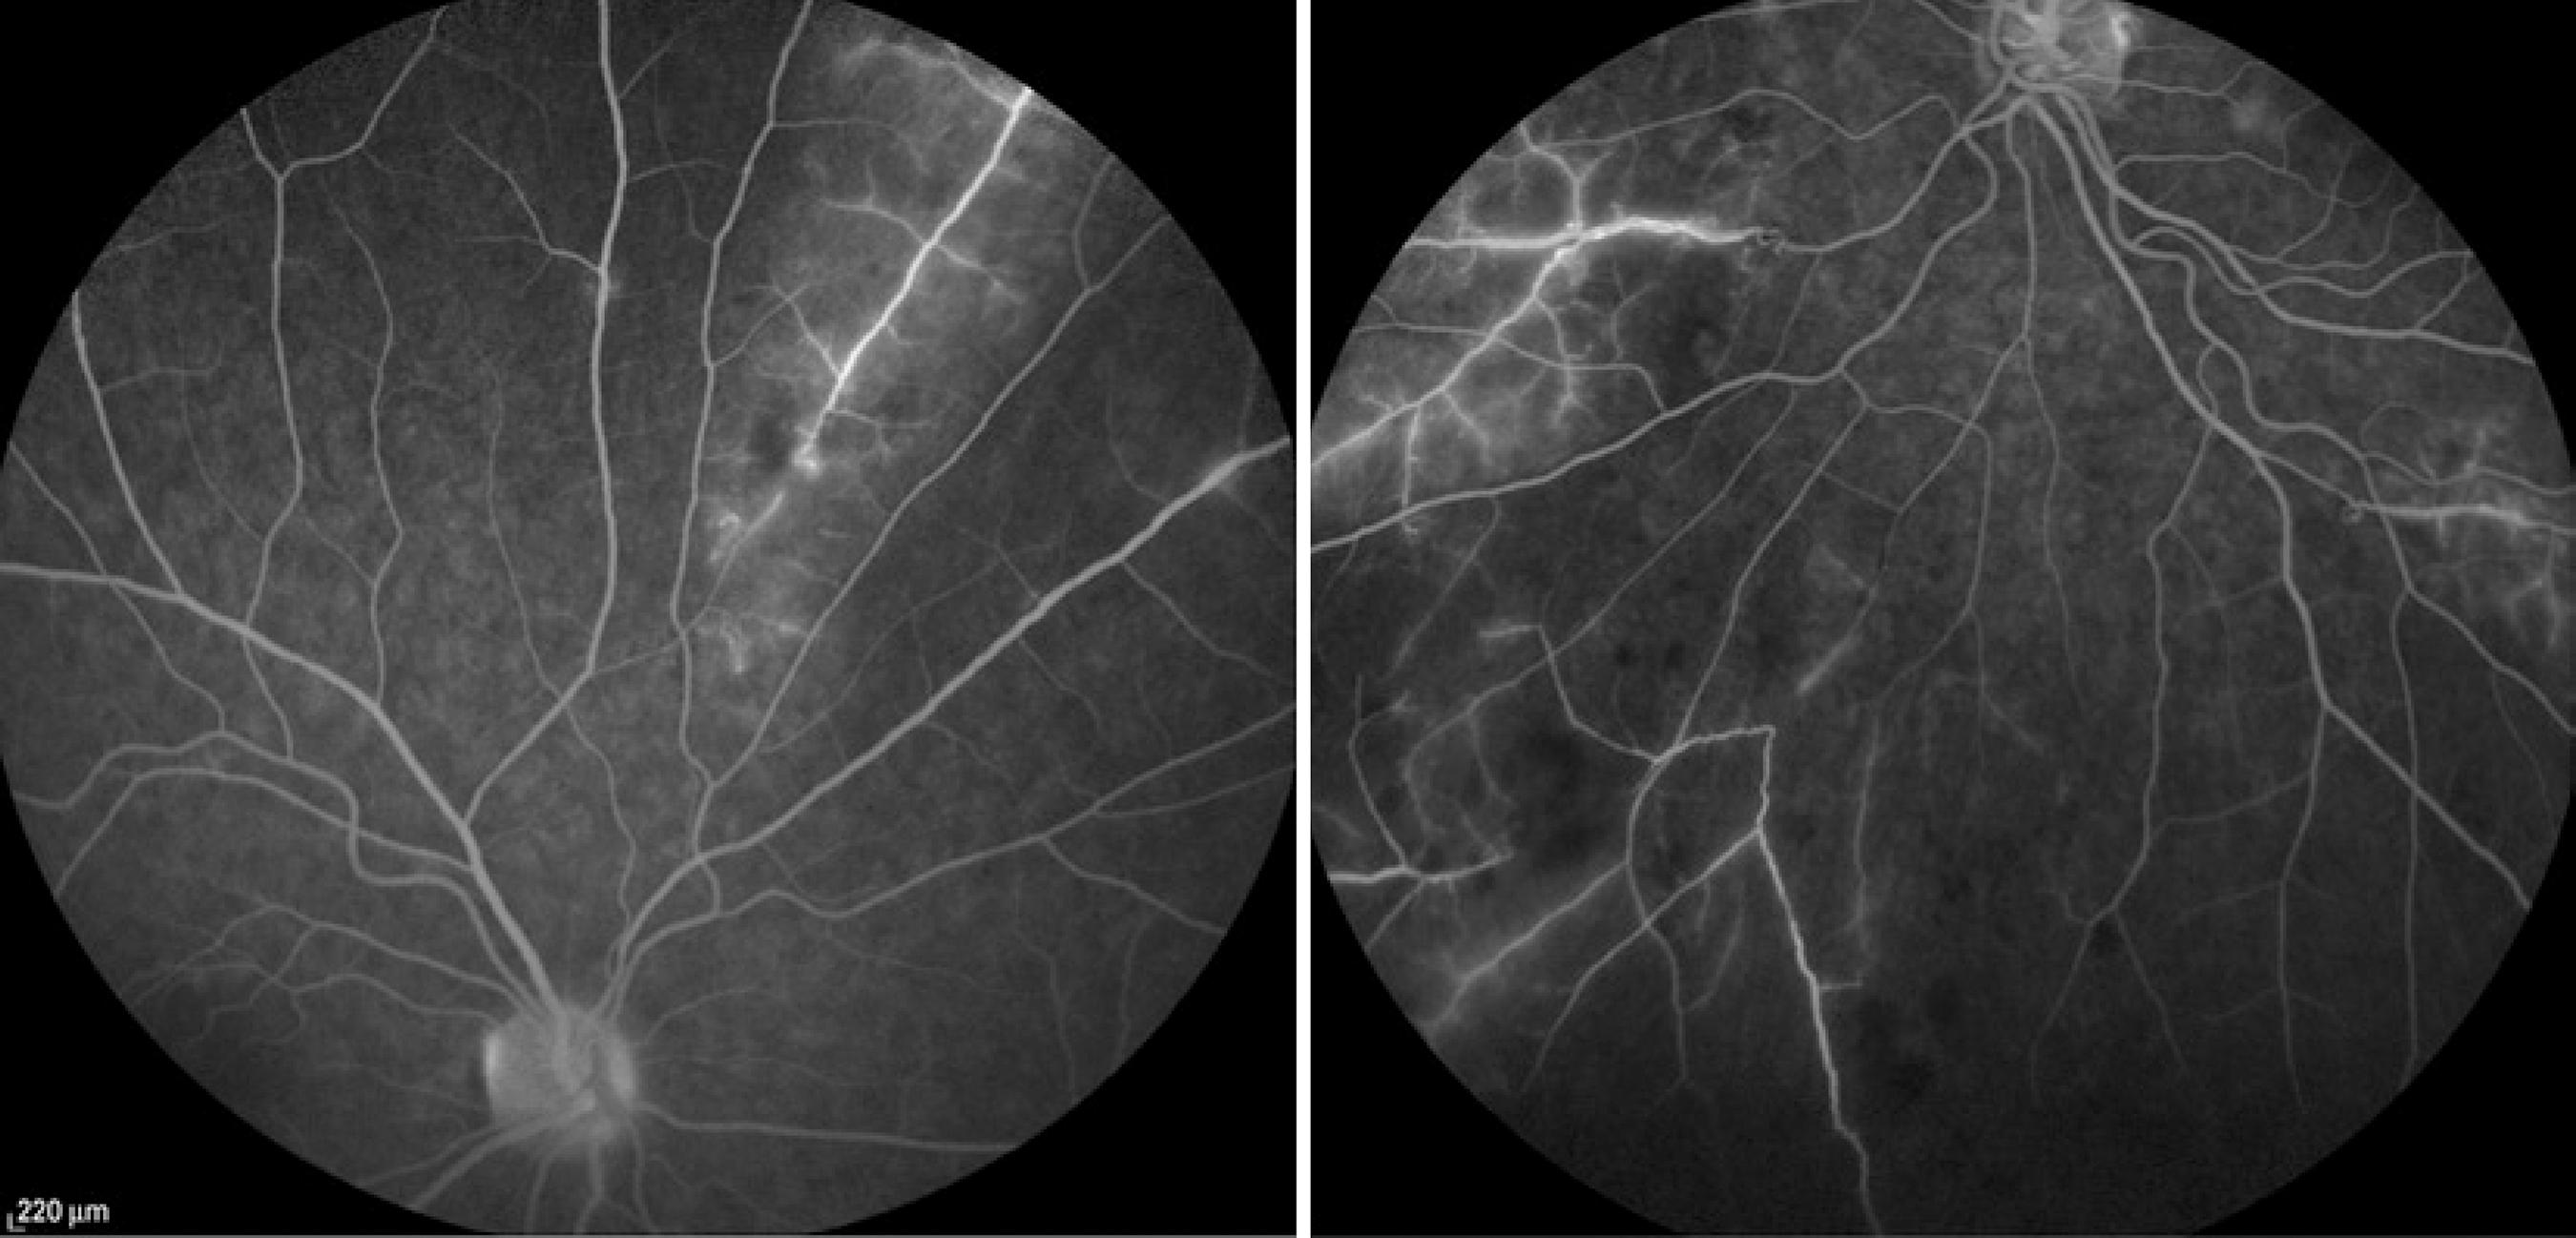

A 27-year-old Afro-descendant woman complained of headache, asthenia, night fever, and bilateral painful upper eyelid edema for 2 months. She also had bilateral ocular pain for 7 days. Her personal and familial past histories were unremarkable. Her best-corrected visual acuity (BCVA) was 20/20 in both eyes (OU). She presented with bilateral superior temporal eyelid edema, and anterior biomicroscopy revealed conjunctival injection and anterior chamber cells 3+(1), without other alterations in OU. The intraocular pressure was normal in OU, and fundoscopy showed vascular sheathing, mainly venous, with candle wax drippings sign in OU, and intraretinal hemorrhages in the left eye (OS) (Figure 1). Testing showed positive serology for to xoplasmosis detected by immunoenzymatic enzyme-linked immunosorbent assay (IgG >650 and IgM= 2.78), anergic PPD, but no other laboratory abnormalities. Fluorescein angiography showed perivascular hyperfluorescence by leakage (Figure 2).

Figure 2 Fluorescein angiography showing hyperfluorescence areas through leakage and capillaritis in both eyes. OD in the right and OS in the left.